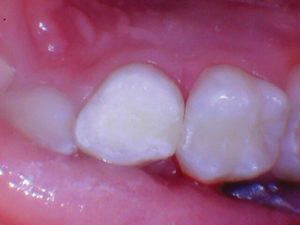

Caso 1

Un paciente de 8 años presentó descomposición de OD en un primer molar primario con síntomas de pulpitis reversible. El diente fue el tratamiento planificado para una restauración de OD con Activa Bioactive Restorative (Pulpdent). Tras la excavación por descomposición, se produjo una exposición pulpar que requirió una pulpotomía terapéutica. Debido a la edad del paciente, me sentí cómodo con una pulpotomía terapéutica con Biodentine (Septodont) seguida de una restauración estética. Si el paciente hubiera tenido entre cuatro y cinco años, me habría restaurado con una corona de acero inoxidable debido a su historial comprobado de longevidad.

Figura 1 Vista preoperatoria del primer molar primario superior. |